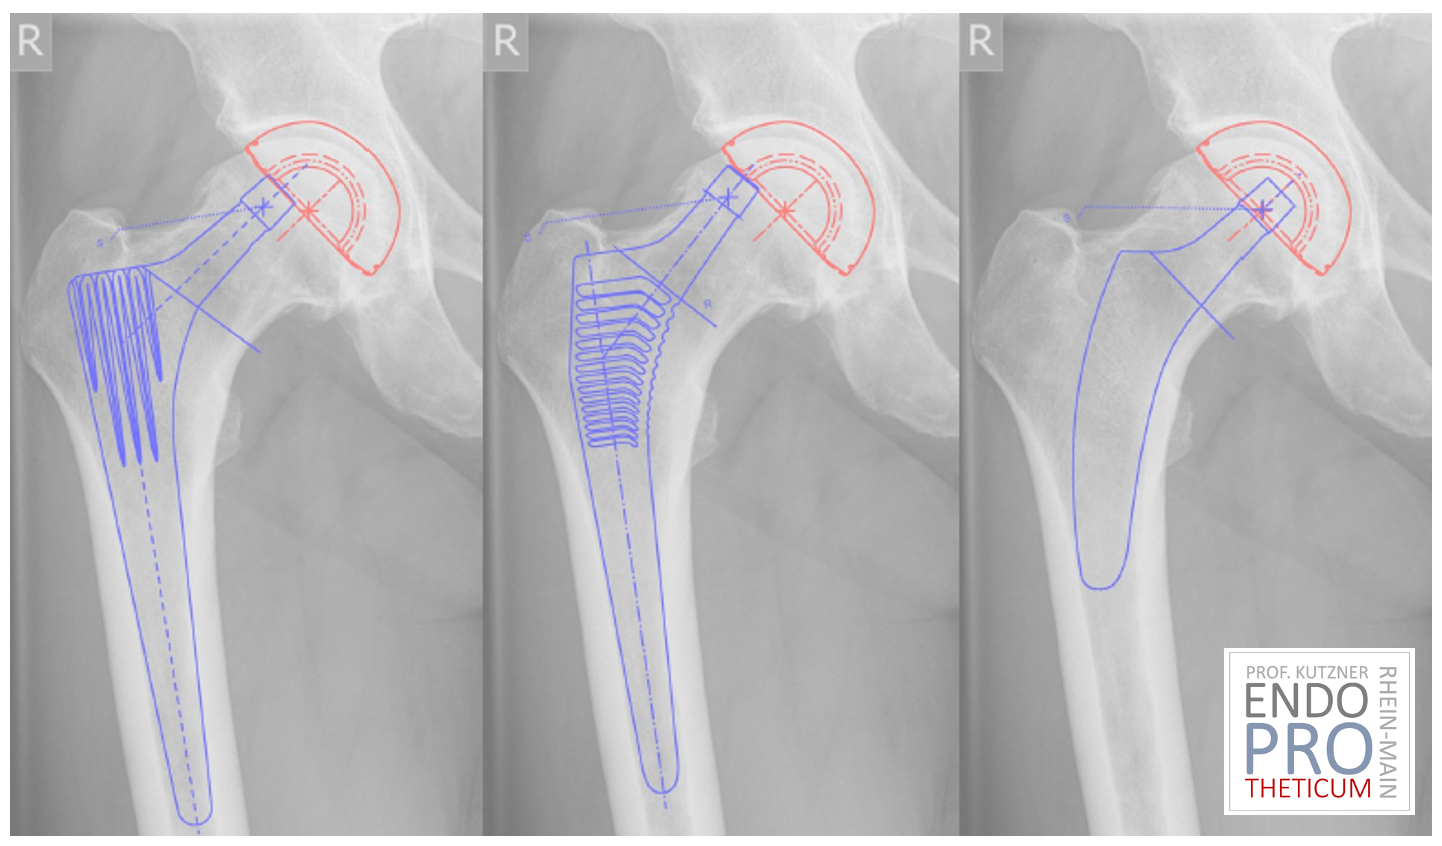

The benefits of short-stem prostheses compared to traditional implants

Benefits of short-stem prostheses

When it comes to treating hip problems, patients are often faced with the difficult decision between different treatment options. In recent years, short-stem prostheses have become a popular choice as they offer a number of advantages over traditional implants. In this article, we take a closer look at the benefits of short-stem prostheses and why they might be the better option for many patients.

In contrast to conventional implants, short-stem prostheses often require less bone removal during surgery. This can help preserve the integrity of the femur and reduce potential complications such as bone loss or femoral fractures. Furthermore, less bone removal can improve the chances of a later revision of the prosthesis, if necessary.